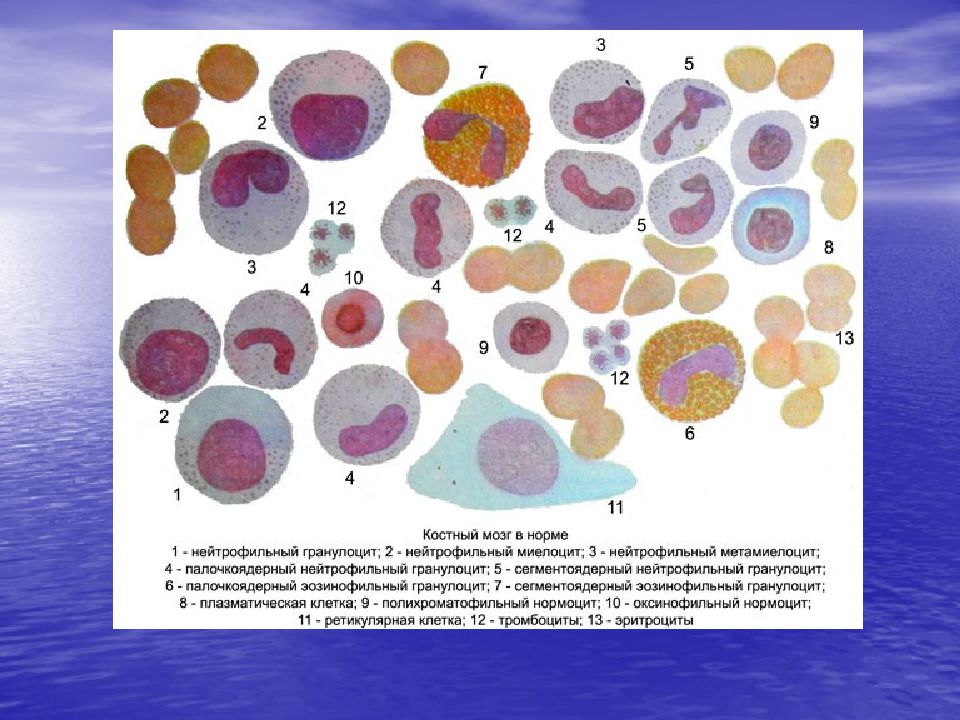

Изучение костного мозга: анатомия и функции